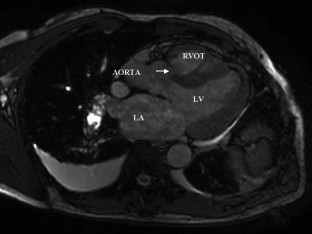

Figure 1